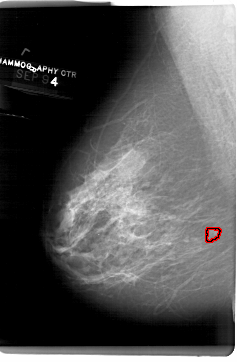

A_1514_1.LEFT_CC

LEFT_CC LINES 6871 PIXELS_PER_LINE 4381 BITS_PER_PIXEL 12 RESOLUTION 43.5 OVERLAY

FILE: A_1514_1.LEFT_CC.OVERLAY

TOTAL_ABNORMALITIES 1

ABNORMALITY 1

LESION_TYPE MASS SHAPE IRREGULAR MARGINS ILL_DEFINED

ASSESSMENT 4

SUBTLETY 2

PATHOLOGY BENIGN

TOTAL_OUTLINES 1

BOUNDARY